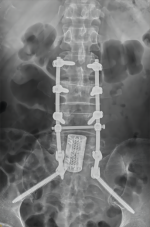

8. 机器人导航辅助下脊柱侧弯矫正技术

脊柱侧弯是一种复杂的脊柱三维畸形,其中以青少年特发性脊柱侧凸最常见。皇冠娱乐城

在浦口地区率先开展机器人导航辅助下脊柱侧弯矫正术,实现了脊柱侧弯手术准确、微创、智能化的突破,获得了良好的效果。还有老年人退变性侧弯,机器人亦可精准置入困难椎弓根螺钉,误差只有0.3mm。